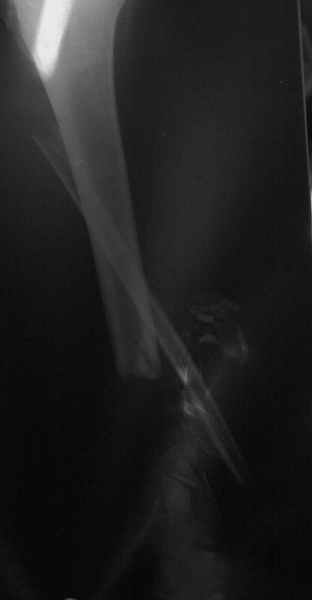

Dorogie kollegy,Have a nice day,Ja bi hotil obsuzdat' s Vami dvuh bolnih, kotorie postupili segodnjia ko mene. Pervy iz nih (OI) bolnoi s otkritoi tiazeloi mehanicheskoi travmoi Rt. leg segment v rezultate DTP, ot chego on imeet sledueshie povrezdenjia:- Otkrity perelom kostei pravoi goleny v srednei i niznoi ee trety s poteriem okolo 10 cm. kostnogo veshestva ot bolshebersovoi kosty, - Povrezdenjia a.tibialis post. s massivnim povrezdeniem zadneoi gruppy musculs goleny,- Malobersovjia kost' imeet segmentarny perelom, ee nizny fragment (kak Vi videte na foto) vistupaet na kozy okolo VNUTRENNOI Lodizky! - Traumaticheski Shock 2-3Drugih povrezdenjia net.

Nemedlenno bolnoi bil' intubirovan i provedeny vse protivoshokovie procedury, pravjia golen' bila pomeshenjia na apparat' Storm, dla reduksii kostei posle ee fiksasii k apparatu s pomoshio 2 spitsy 3mm D. Provedena Repozitsia pereloma i fiksirovana STORMOM vremenno, za tem sosudisty hirurg vypolnil 2 obhodnih anastomosa for a. Tibilis posterior, bili udaleny bolshie chasty iz musculov zadnoi gruppy goleny v predelah "vozmozno vedemih" zdorovoi tkany, oblast' pereloma promita by N. sol. 0.9% - 12 L. Zatem byla proizvedena okonchatenjia reduksia pereloma posle umerennoi traksii goleny na apparate, i fiksasiya pereloma s pomoshio apparata vneshnei fiksasii. Tak, Kakie soobrazanjia po dalneshemu vvdenjia bolnogo? On poluchaet antibiotiky i bolshie dozy LMH (Clexane 80 X 2) i vse ostalnoe......